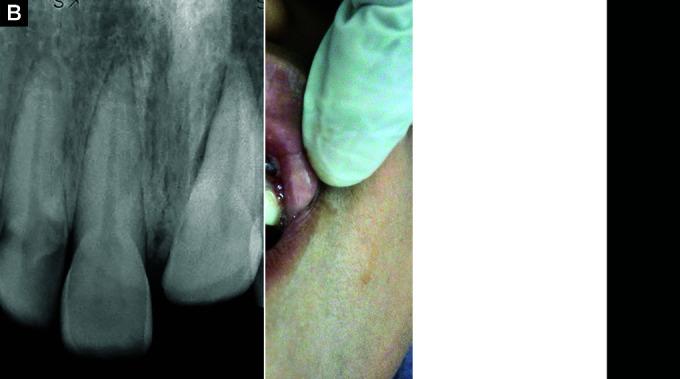

A 9-year-old female patient suffered intrusion injury to 21 with no root fractures. Since intrusion was severe type, surgical repositioning with flexible splinting is done. Complications such as alveolar bone loss and gingival recession have occurred, which were successfully treated with PRF. To prevent development of resorption, calcium hydroxide was used as intracanal medicament and doxycycline was used to prevent surface resorption.

一名9岁女性患者的21号牙发生嵌入性损伤,无牙根骨折。由于是严重型嵌入,遂进行了手术复位并采用弹性夹板固定。出现了牙槽骨吸收和牙龈退缩等并发症,使用PRF成功治愈。为防止吸收的发生,根管内使用氢氧化钙,并用强力霉素预防表面吸收。